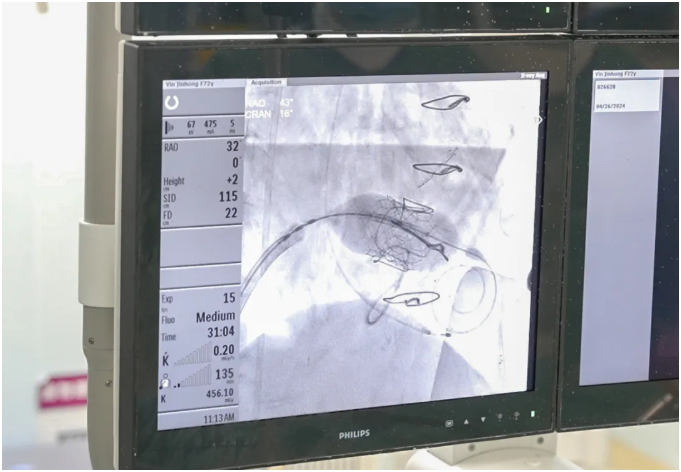

张戈军教授、韩宇主任大胆精准操作,细长灵巧的导丝从股静脉出发,建立生命通道,经过房间隔、跨瓣,准确地把人工瓣膜输送到预定位置。

造影结果显示,新置入的二尖瓣启闭正常,无任何反流,整个关键手术过程仅用时40分钟。